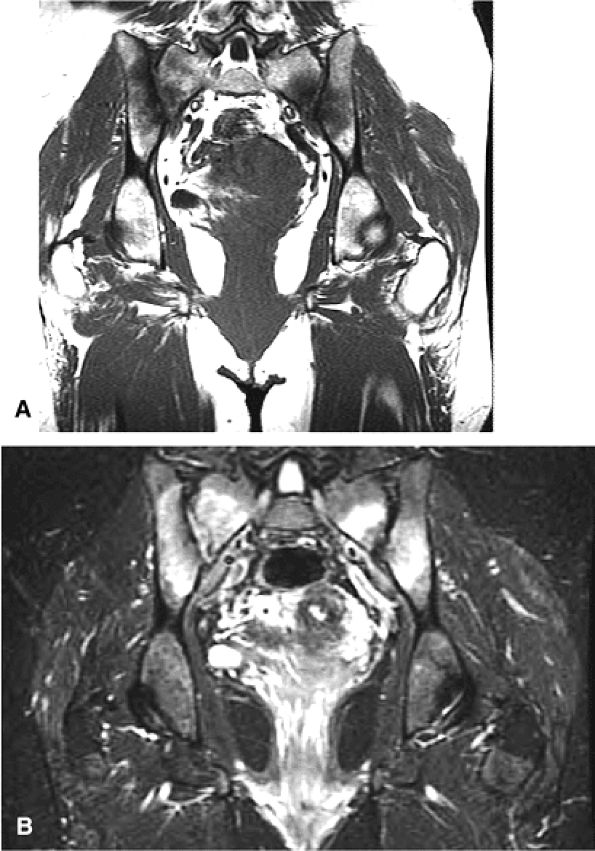

FIGURE 3.28 ● Normal coronal anatomy of the hip. (A, B) In the setting of pubic rami fractures, the sacrum and sacroiliac joints should be examined for the presence of fractures or a diastasis completing the pelvic ring fracture. (C, D) Sacral insufficiency fractures or sacroiliitis is seen only on images with a large field of view. Occasionally they are the only significant finding in a patient with unilateral hip pain. (E, F) Images with a large field of view should also be used to examine the pelvic viscera, especially in women, for adenopathy, masses, and adnexal or uterine pathology. (G, H) Articular cartilage covering the acetabulum and femoral head is clearly displayed. A small portion of the medial femoral head (the fovea) and a large portion of the medial acetabulum (the acetabular fossa) are devoid of cartilage. (I, J) Early signs of degenerative arthrosis may be seen in the anterior superior quadrant of the hip, including cartilage thinning and fraying, subchondral edema in the anterosuperior acetabulum, and anterosuperior labral tearing. (K, L) The anterior superior portions of the bilateral acetabuli are visualized on images obtained with a large field of view. These images allow appreciation of subtle differences in symmetry of the acetabular contour. Even mild acetabular dysplasia may be accompanied by unilateral labral tears and chondral degeneration. (M, N) Osseous spurring at the symphysis pubis is a common finding. Occasionally, acute or insufficiency fractures occur immediately to the left or right of the symphysis pubis, and are seen only on images obtained with a large field of view.